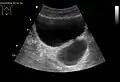

Diverticulum of the urinary bladder of a 59-year-old man, transverse plane -

Bladder diverticula as seen on ultrasound with doppler[18]

Bladder diverticula as seen on ultrasound[18]